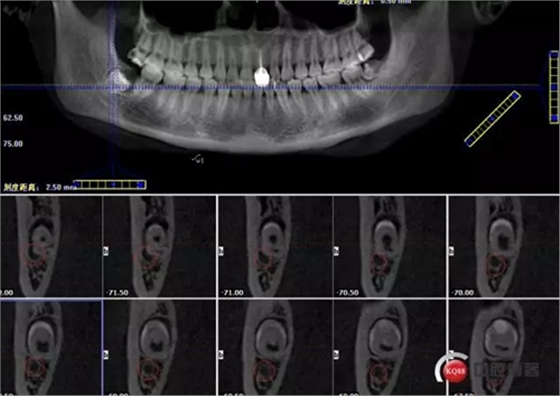

牙齒上1/3CT切片,神經(jīng)管在下方

1498615726_560454.png

牙齒中1/3神經(jīng)管偏頰側(cè)